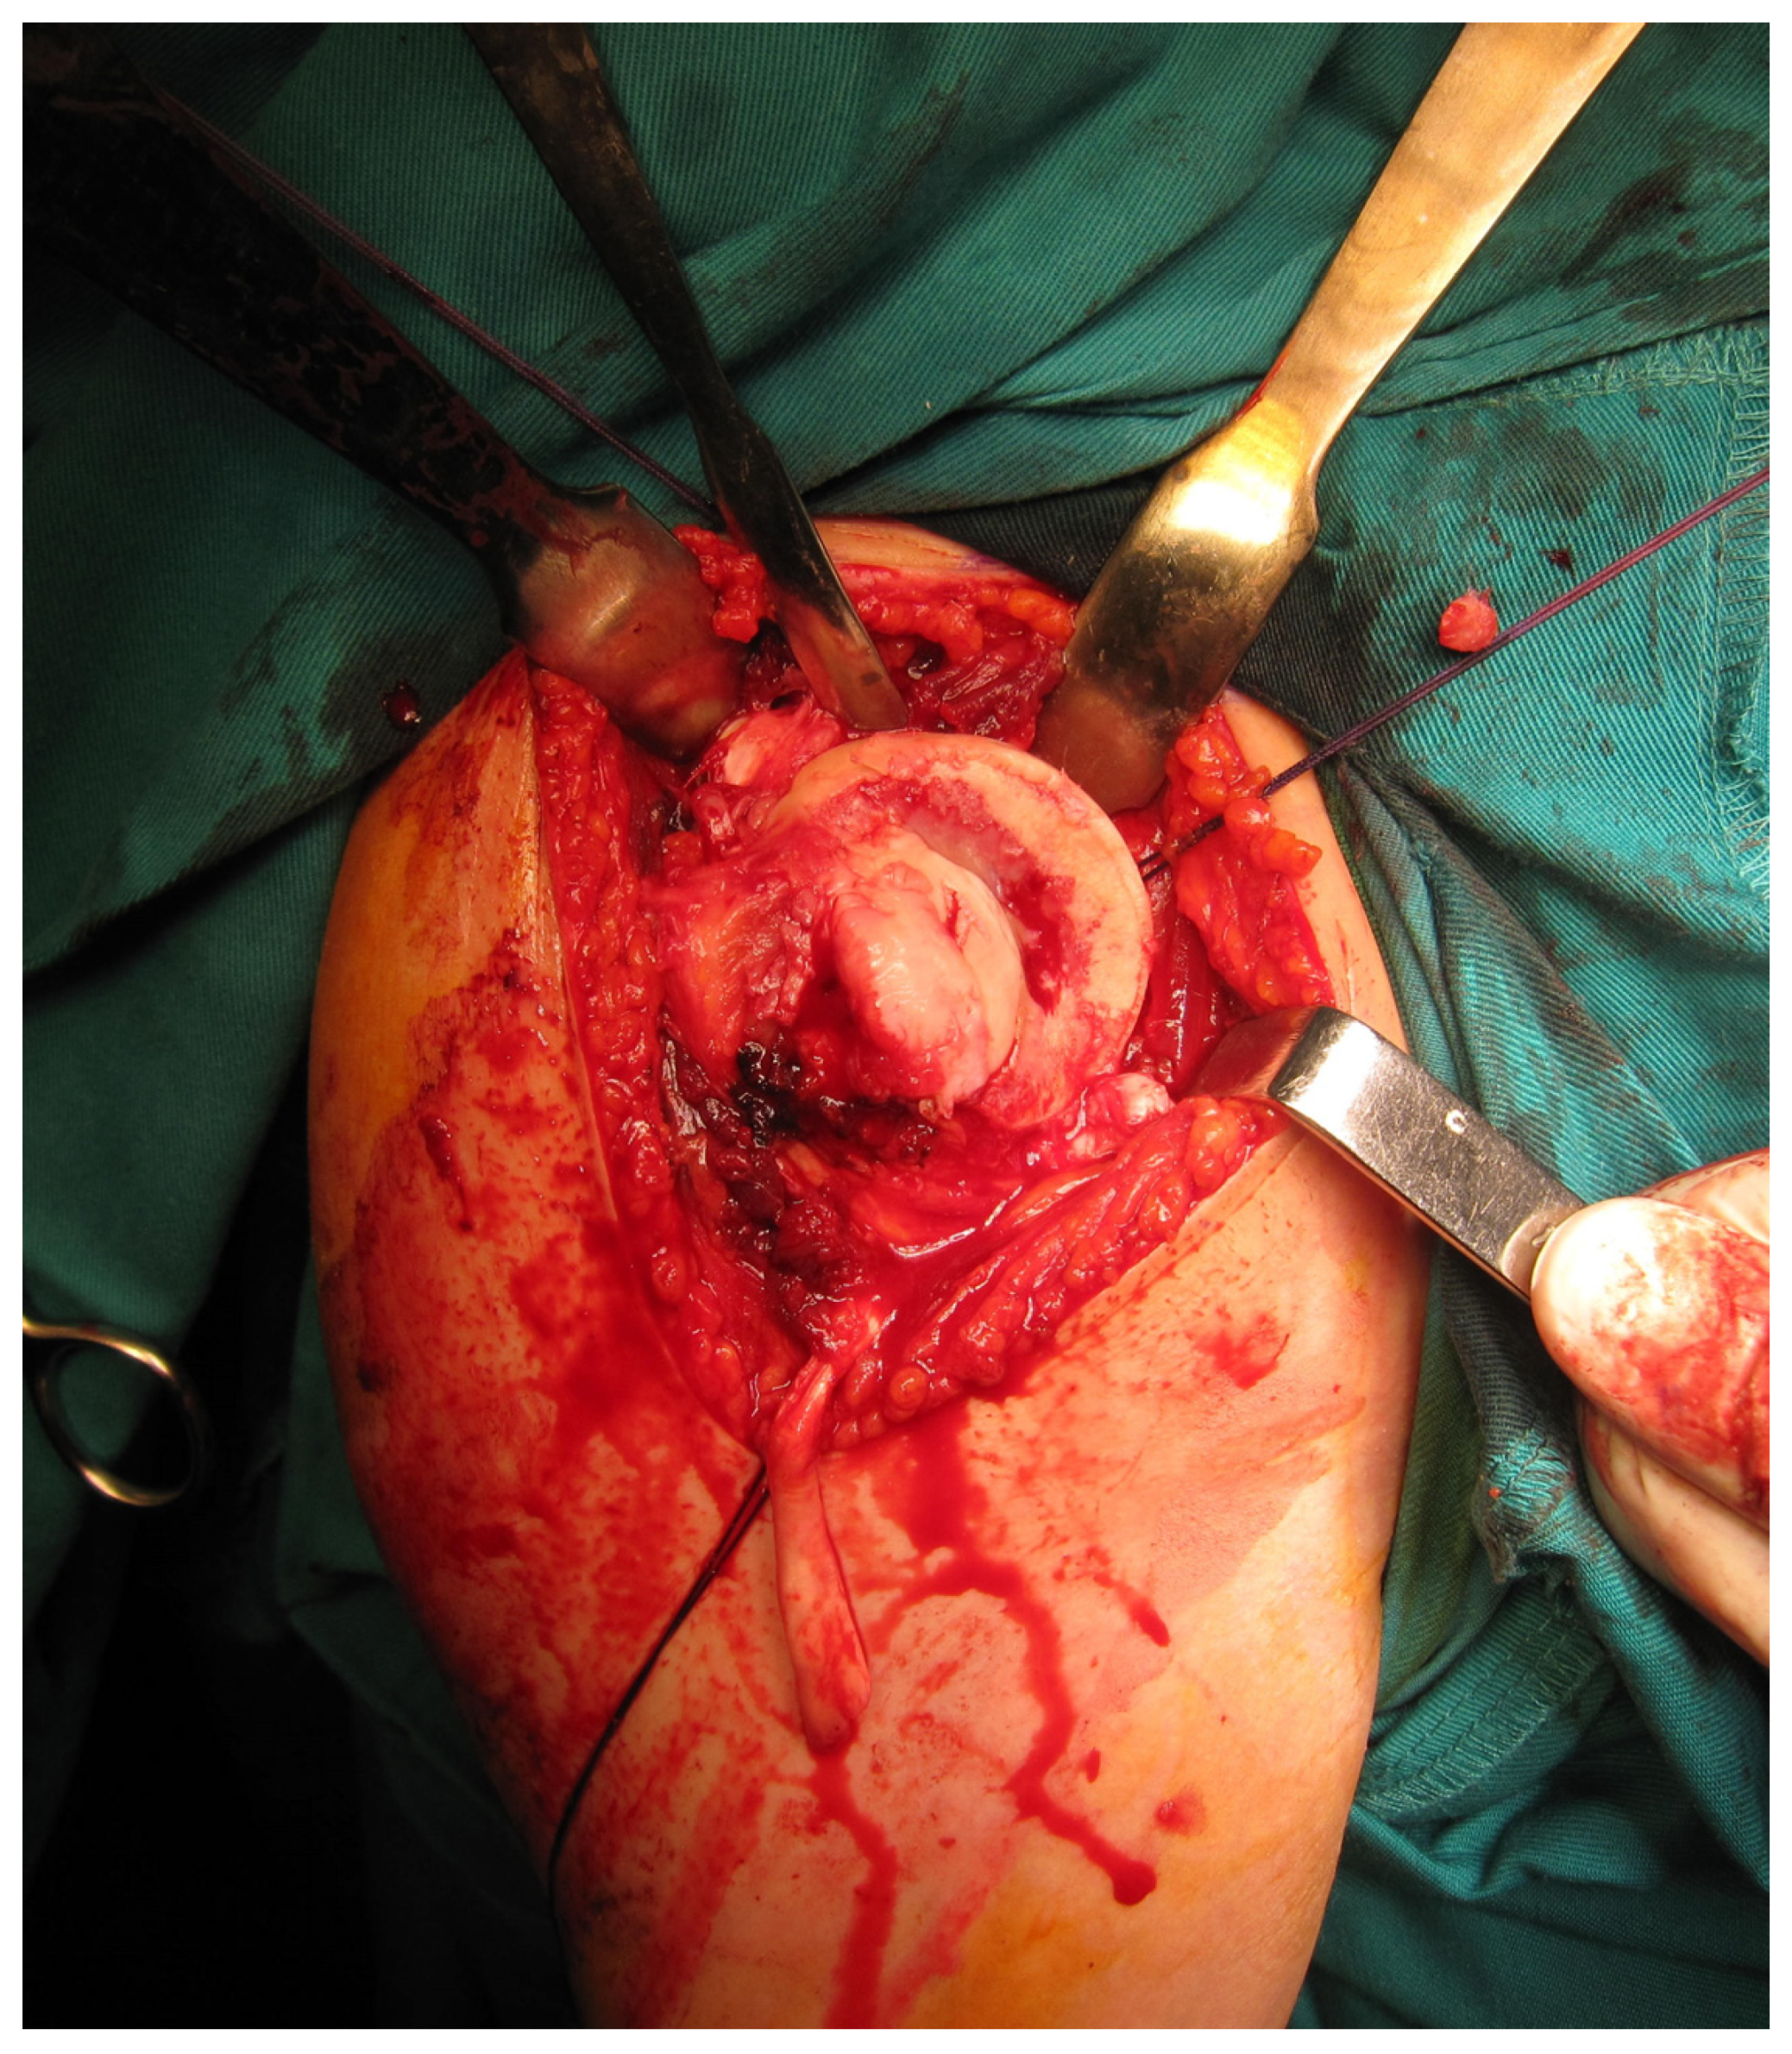

All femoral condyle osteochondral allografts were fresh-frozen and stored at −80 °C. They were tested for bacterial contamination, as well as serologically for hepatitis (A, B and C) and human immunodeficiency virus. On the day of surgery, the osteochondral grafts were thawed and submerged in 300 mL of saline solution with five ampoules of 120 mg gentamycin. Before placement, the grafts were washed with 500 mL of pure physiological solution. An oscillating saw was used to prepare the humeral head defect site for the osteochondral allograft. The dimensions of the lesion were carefully measured, and a similarly sized allograft was modeled accordingly (Figure 2 and Figure 3). Tenodesis of the long head of the bicep tendon was performed in all patients. Fixation of the allograft to the humeral head was achieved using two cancellous screws in four patients, while two Herbert screws [8] were used in the remaining sixteen patients, all placed subchondrally (Figure 4). After the shoulder joint was reduced into place, the reinsertion of the m. subscapularis was performed in its anatomical position (because osteotomy of the lesser tubercle was performed during the procedure). During the immobilization period, the m. subscapularis healed in its anatomical position. The shoulder joint capsule was sutured with absorbable sutures and the wound was closed in layers.

Figure 2. Intraoperative presentation of a reverse Hill–Sachs lesion (photo from the personal archive of intraoperative photos of the author).